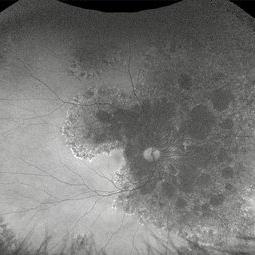

Intriguing Web

Aug 28 2024 by Hemanth Murthy, MBBS, MD, FASRS

Right eye of a 43 year female patient came with blurring of vision of right eye since 2 years. There was loose redundant skin in the neck and axilla. Angiod streaks were in a spider web appearance .Vision was 1/60 in right eye and 6/9 in left eye. Right macula showed a sub retinal scar with pigmentation.

Photographer: Mr Veda Vyas

Imaging device: Optos Daytona

Condition/keywords: Angiod streaks in Pseudoxanthoma elasticum